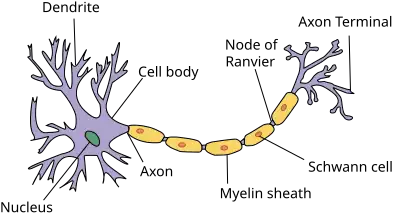

The brain is mainly composed of neurons (cells that can transmit electrical signals) and supporting cells (glia). As for most other organs, there are blood vessels and immune cells too. Neurons have a main body and many extensions.

Dendrites are extensions of a neuron that receive signals and then the axon transmits electrical signals to other neurons. The main body is a bit darker than dendrites or axons and is predominantly located in the grey substance, thereby giving it its color. Axons are covered by white fatty substance (myelin sheath made up of lipids) and makes the white matter of our brains.

The brain connects to other organs by means of long nerves that are comprised of neurons. Electrical signals trigger reactions in connected organs, whereas sensory nerve endings (dendrites or other specialized structures) help to collect input. For example, in muscles electrical signals are converted into chemical signals eliciting muscular contraction via the sliding filament hypothesis.